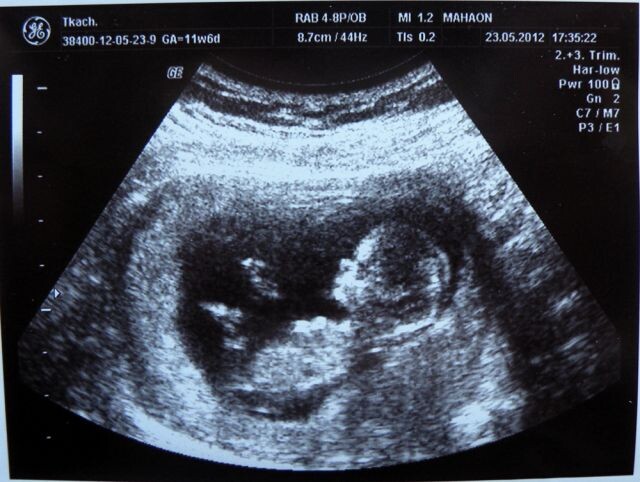

Умчалась в ближайшую клинику. Впопыхах, что ей срочно, очень, пропустите. И снова узи... И,....

...Чего вы ревете, мамочка, вам волноваться нельзя! Сердце Саши замерло... Неужели??? Как так??? Рой вопросов - скажите,точно бьется сердечко? Узистка развернула экран - сами смотрите, если не верите! Вот она, крохотная точка пульсирует на экране - целый мир Сашиной жизни. Ее Вселенная!